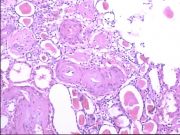

| 2021年12月10日 (五) 13:22 | 24号切片-小叶性肺炎-镜下观2-见细支气管.jpg (文件) |  |

209 KB | Cirno.9 | 基于MsUpload的文件上传 | 1 |